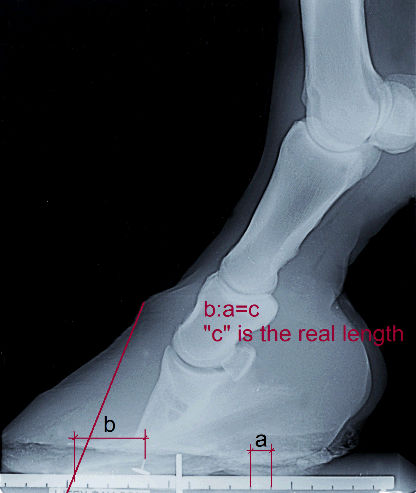

Die patentrechtlich geschützte Lösung zur leichten und exakten Ausmessung ihrer

analogen und digitalen Röntgenaufnahmen.